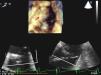

PTV was performed with general anesthesia and orotracheal intubation, and was monitored with real-time three-dimensional (RT3D) transesophageal echocardiography (TEE). In mid-esophageal plane at 25° with simultaneous multiplanar visualization (x-plane mode), long- and short-axis images of the tricuspid valve were obtained. In RT3D mode of the complete volume and using the cropping tool, a view of the tricuspid valve was then obtained from the right atrium (Figure 1). The maximum diameter of the annulus in long- and short-axis views was 30 and 20 mm, respectively.

The approach was via the right femoral vein, and the tricuspid valve was crossed by a Glidecath MP catheter (Terumo Medical Corporation) and a straight guidewire. This was replaced by a pigtail catheter, and transvalvular gradients of 15 mmHg were observed. A stiff guidewire (Amplatz Super Stiff, Boston Scientific) was placed over this catheter, and a 30 mm×4 mm balloon valvuloplasty catheter (Tyshak, Numed Inc.) was introduced. Inflation was monitored by fluoroscopy (Figure 2) and RT3D-TEE. After inflation, a transvalvular gradient of 2.8 mmHg was measured by echocardiography. No tricuspid regurgitation was observed.